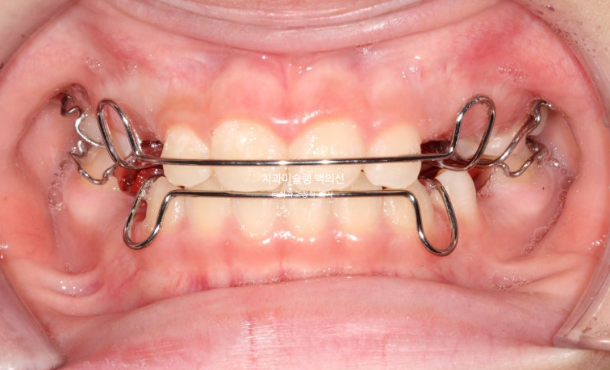

프리올소 라는 장치는 프랑켈 장치의 최신 간단 버전 쯤으로 생각하시면 편합니다.

아래턱의 위치를 간단하게 잡아주는 장치인데 앞니가 거꾸로 물리는 반대교합에서 간편하고 빠른 효과를 냅니다.

프리올소 권유드렸고 2달만에 앞니 반대교합은 해결이 되었습니다.